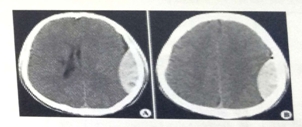

試題2:男,44歲。頭部外傷12小時(shí)。結(jié)合CT片,此診斷為(2分)

答案:C